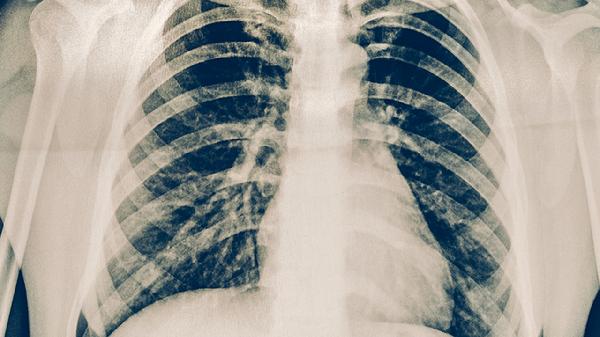

艾滋病患者、长期使用免疫抑制剂者如器官移植术后、糖尿病患者及恶性肿瘤患者等群体,由于免疫功能受损,更易感染结核菌或使潜伏感染复发。临床表现为乏力、体重下降伴呼吸道症状时,需进行胸部X线及痰涂片检查。常用抗结核药物包括异烟肼片、利福平胶囊、吡嗪酰胺片等。